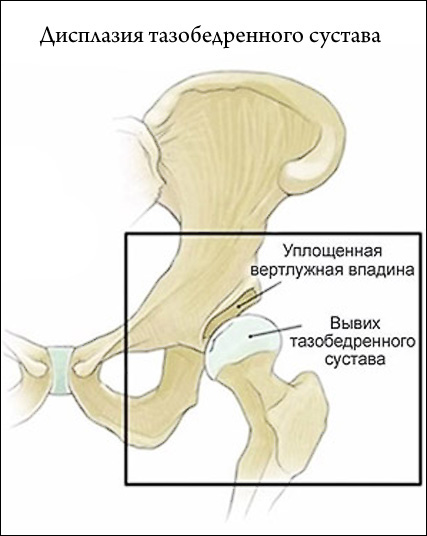

Огляд дисплазії тазостегнових суглобів у новонароджених: причини, діагностика, лікування